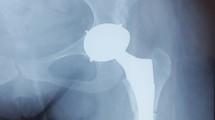

Routine measures are taken to prevent infection and anticoagulation is administered postoperatively. The affected limb is maintained in neutral abduction and extension position after surgery. On the first postoperative day, follow-up X-rays of both hips in the anteroposterior and lateral views, along with full-length anteroposterior and lateral views of both lower limbs are obtained (Fig. 6D). Passive and active exercises are initiated for the affected limb to improve quadriceps muscle strength and prevent joint dislocation. For the 3D group, standing and walking with assistance may be initiated on the first postoperative day after the follow-up examination. For the Non-3D group, crutch-assisted ambulation is recommended for the first week postoperatively, followed by full weight-bearing at 4–8 weeks after the follow-up examination.

Intraoperative images and postoperative X-rays of a patient from the 3D group. (A): Patient positioning and incision marking. (B): Intraoperative reconstruction of the positioning of acetabular and Augments prostheses based on three-dimensional modeling and 3D models. (C): Intraoperative installation effect of Augments prostheses, acetabular prostheses, and acetabular liners. (D): Postoperative first-day bilateral hip anteroposterior X-ray images of the patient.